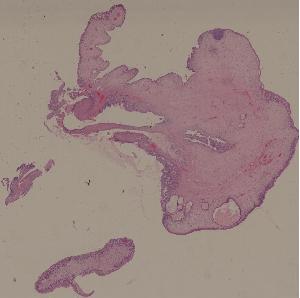

23.炎性息肉